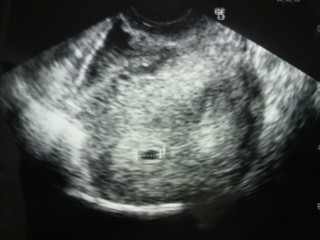

初診はなにも見えず2回目にして12.2mmになってました★ めちゃ嬉しかった^ ^次二週間後に心拍確認! 無事生まれてきますように!